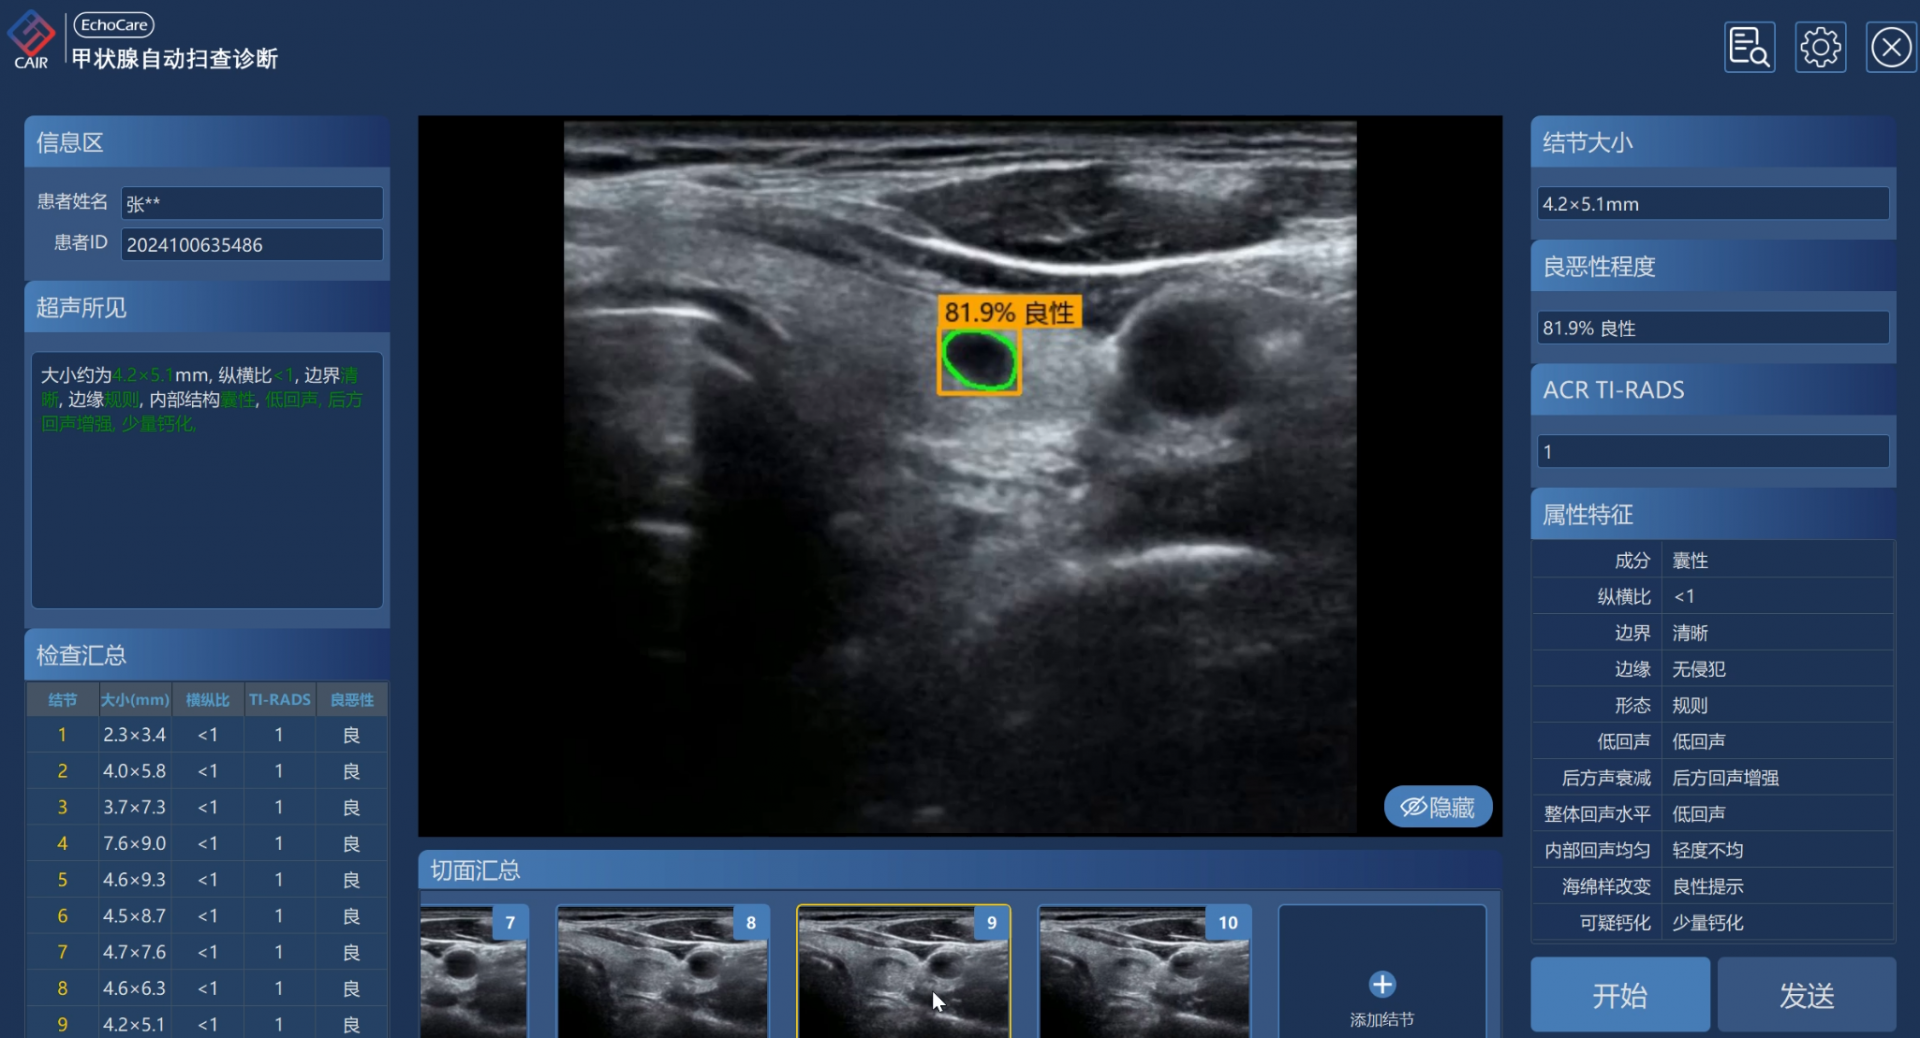

疾病诊断与筛查,可用于多种疾病的诊断和筛查,包括妇产科卵巢肿瘤良恶性分类、甲状腺结节检测与良恶性分类、心脏超声主动脉瘤检测与分析等。

EchoCare“聆音”通过对结节的影像特征进行智能识别与量化分析,可有效减少人为差异,提升检出效率与分类一致性,为早期诊断与个体化治疗决策提供可靠支持。该系统可以促进甲状腺结节的分级诊疗,优化并节约相关医疗成本。